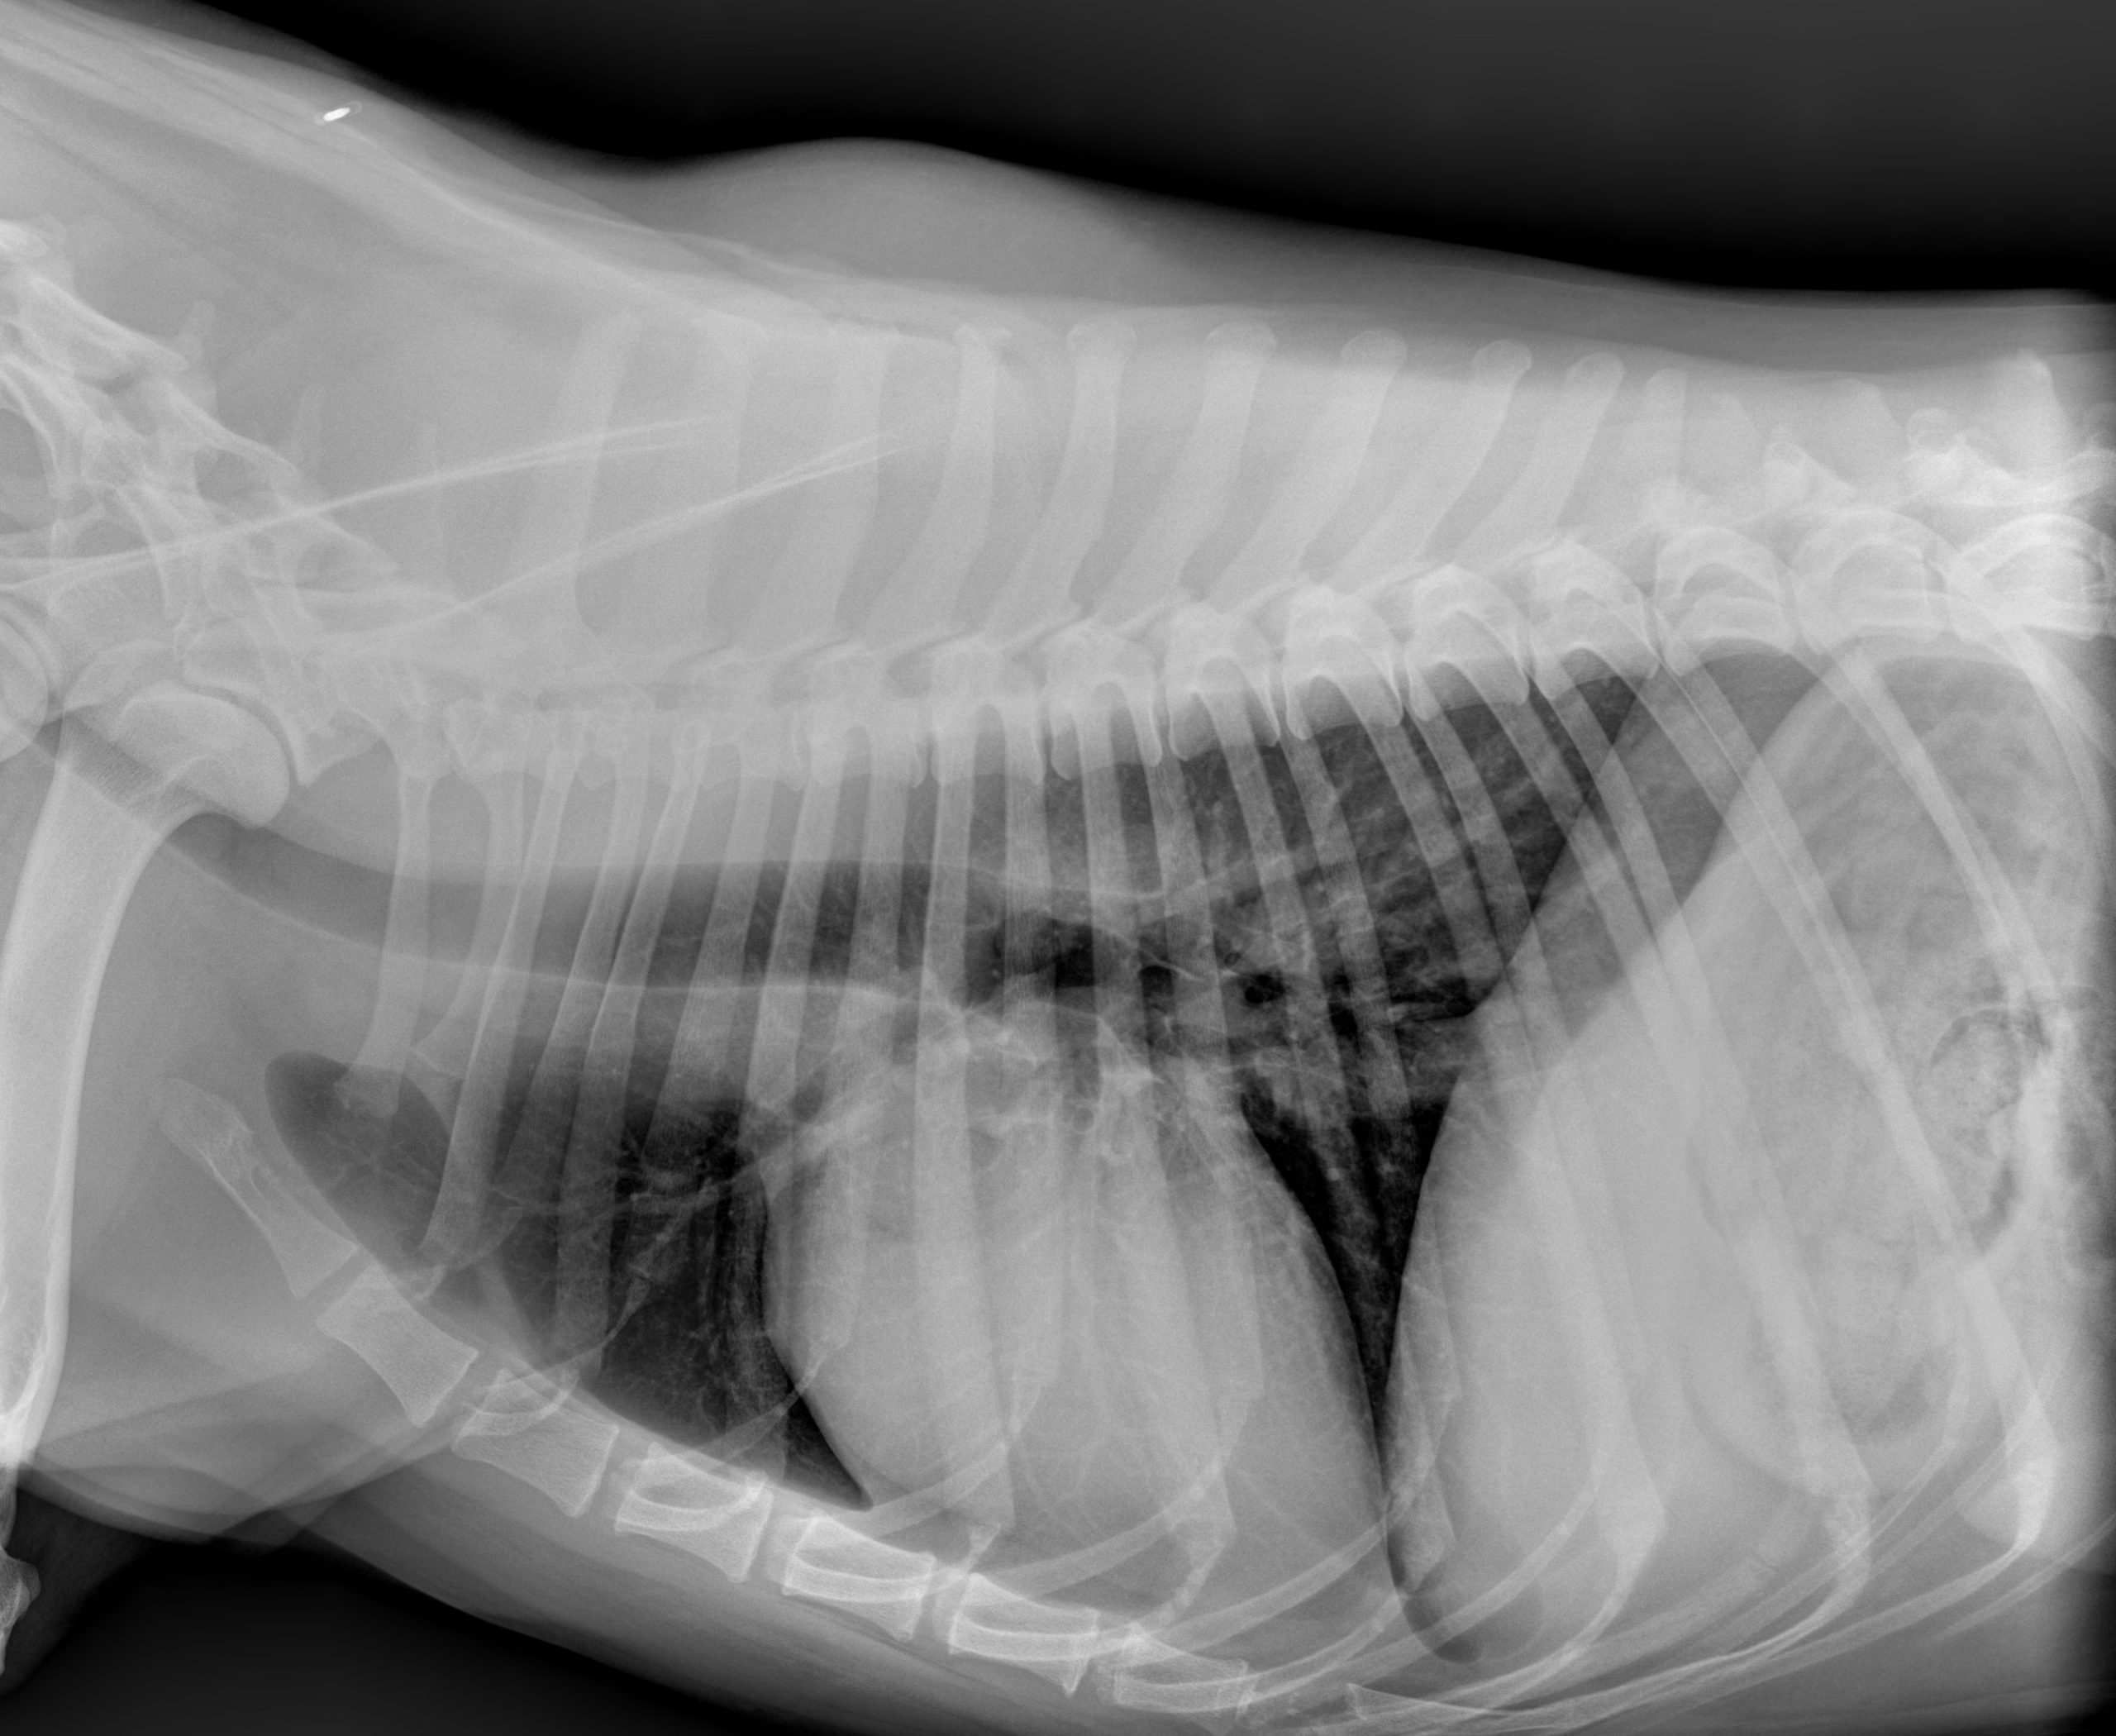

When your pet is hurting, every minute counts. At Veterinary Way Animal Hospital, we utilize top-of-the-line digital radiology equipment to capture high-resolution images of your pet’s internal structures in seconds.

Digital X-rays are a cornerstone of our diagnostic process, allowing our specialty-trained team to perform thorough, in-house evaluations. Compared to traditional film X-rays, digital technology provides clearer images, less radiation exposure for your pet, and the ability to enhance and zoom in on specific areas for a more accurate diagnosis.

- Chest & Heart: Monitoring heart size and shape, as well as evaluating the lungs for pneumonia or tumors.

- Abdominal Issues: Detecting ingested foreign objects (like toys or coins), bladder stones, or enlarged organs.